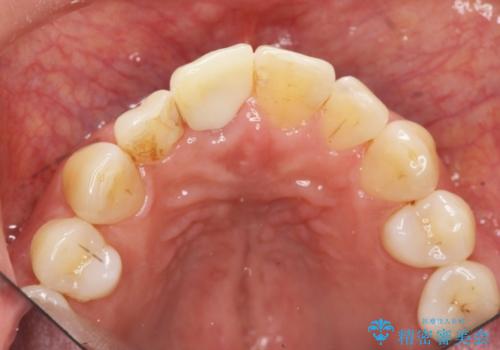

骨造成を伴う前歯のインプラント治療

- 前歯を外傷により失い、審美性の改善を求めて来院されました。

横の歯を削る必要のあるブリッジ治療、着脱の必要な入れ歯に強い抵抗があったためインプラント治療を計画します。

審美的・機能的に良好な位置に埋入するには、骨量が十分ではなかったため骨の造成を併用したインプラント埋入外科手術を行います。

前歯のインプラントを審美的に仕上げるには、インプラント周囲に十分な骨の量と厚みのある歯肉、そして埋入位置の精密な位置付けが重要です。